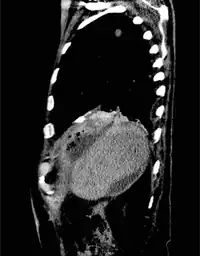

| Duodeno Biliary Fistula | |

For bronchobilary fistula, the following tests are performed: 1) ultrasound abdomen, may show subdiaphragmatic collection around the surface of the right lobe of the liver. 2) preoperative chest X-ray, may demonstrate mild to moderate right-sided pleural effusion without an active lung pathology. 3) CT scan, may reveal focal collection along the liver's right lateral margin, which can be communicating with one of the right lower lobe bronchi, supporting the diagnosis of a BBF.[1]